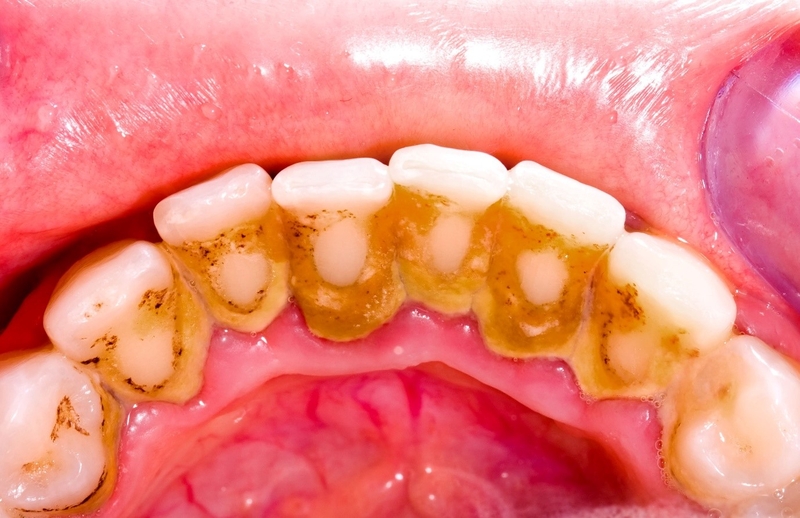

Cao răng (vôi răng) bản chất là sự kết hợp giữa muối canxi và phosphate, được hình thành từ các vụn thức ăn, muối trong nước bọt cùng với một số chất khoáng trong miệng, khi soi gương dễ dàng nhận diện qua những mảng bám màu vàng ố hoặc màu nâu đen tại vị trí chân răng.

Nhìn có vẻ vô hại nhưng thực tế lại là nguyên nhân gây mất thẩm mỹ, hình thành nhiều vi khuẩn làm hôi miệng, làm hư men răng và gây sâu răng, nguy hiểm hơn vi khuẩn sẽ gây kích thích và làm hại đến nướu răng dẫn đến các hiện tượng như:

Vi khuẩn còn là nguyên nhân dẫn đến nhiều bệnh nguy hiểm như viêm tủy, viêm niêm mạc miệng và lưỡi, viêm amidan,…